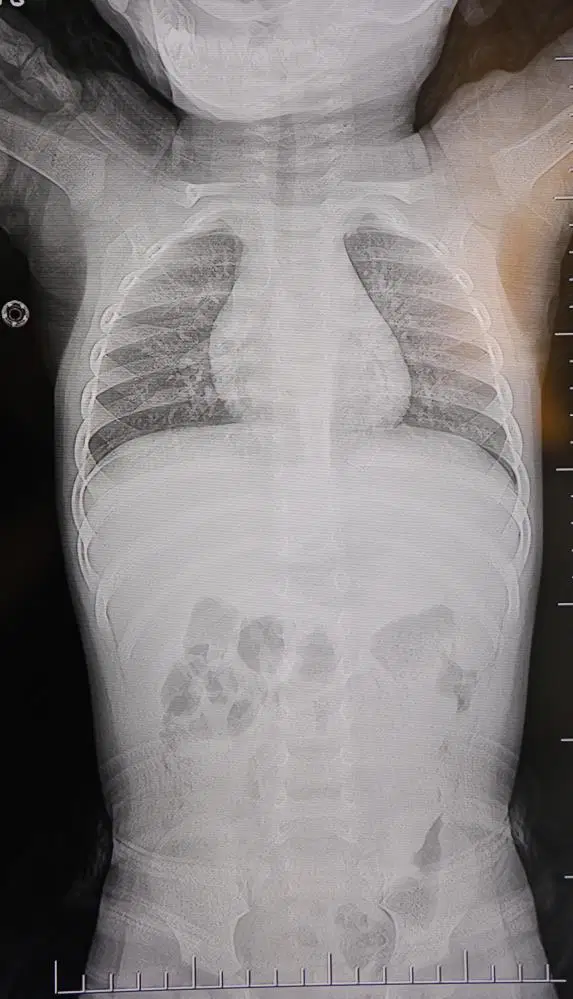

Alınan bilgiye göre, Kahramanmaraş’ta farklı ortopedi, çocuk cerrahisi ve beyin cerrahisi kliniklerine başvurusu yapılan bir yaşındaki bebeğin, sırt bölgesinde yabancı bir cisim olduğu ancak müdahalenin zor olduğu ve 8 yaşına kadar beklenmesi gerektiği bildirildi.

Ailenin başvurduğu hastanede görev yapan Beyin ve Sinir Cerrahisi Uzmanı Prof. Dr. İdris Altun tarafından yapılan tetkiklerde, yabancı cismin cilt altında, omurilik kanalına yakın bir bölgede olduğu ve akciğer zarına doğru ilerlediği belirlendi. Hasta, genel anesteziye alınmadan, lokal anestezi ve sedasyon eşliğinde ameliyata alındı. Yapılan müdahalede yabancı cisim tamamen çıkarıldı. Çıkarılan cismin, ince zımba teline benzer metal bir tel olduğu ve yaklaşık 2 santimetre uzunluğunda bulunduğu tespit edildi. Hasta, aynı gün taburcu edildi.

Konuya ilişkin açıklama yapan Prof. Dr. İdris Altun, “Sırtında yabancı bir cisim olduğu söylenmiş ancak çıkarılamayacağı ve 8 yaşına kadar beklenmesi gerektiği ifade edilmişti. Bize başvurduğunda yaptığımız tetkiklerde, cilt altında, omurilik kanalına çok yakın ve akciğer zarına doğru ilerleyen bir yabancı cisim tespit ettik. Hastamızı tamamen uyutmadan, lokal anestezi ve sedasyon eşliğinde müdahale ederek lezyonu tamamen çıkardık. Çıkardığımız cismin ince zımba teline benzer, yaklaşık 2 santimetre uzunluğunda metal bir tel olduğunu gördük. Bu yabancı cisim alınmasaydı, bölgede enfeksiyon gelişebilirdi. Enfeksiyon sonucu omurilik kanalında ciddi hasarlar oluşabilir, çocuk büyüdükçe cismin hareket etmesine bağlı olarak omurilikte zedelenmeler meydana gelebilirdi. Ayrıca yana doğru ilerleyerek akciğer zarına ve akciğere batma riski vardı. Bu da enfeksiyona ve ilerleyen süreçte tümörle karışabilecek tablolara neden olabilirdi. Şu an hastamız gayet sağlıklı. Gerekli kontrolleri yaptık ve aynı gün taburcu ettik” dedi.